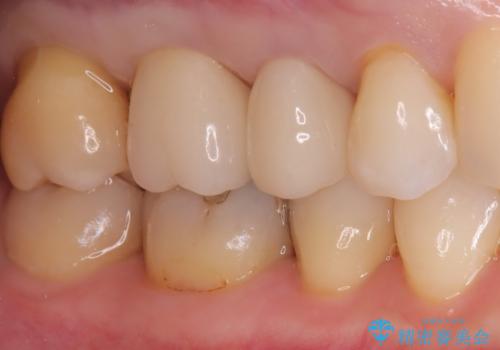

色調も周りの歯に合わせることができ、患者さんには満足していただきました。